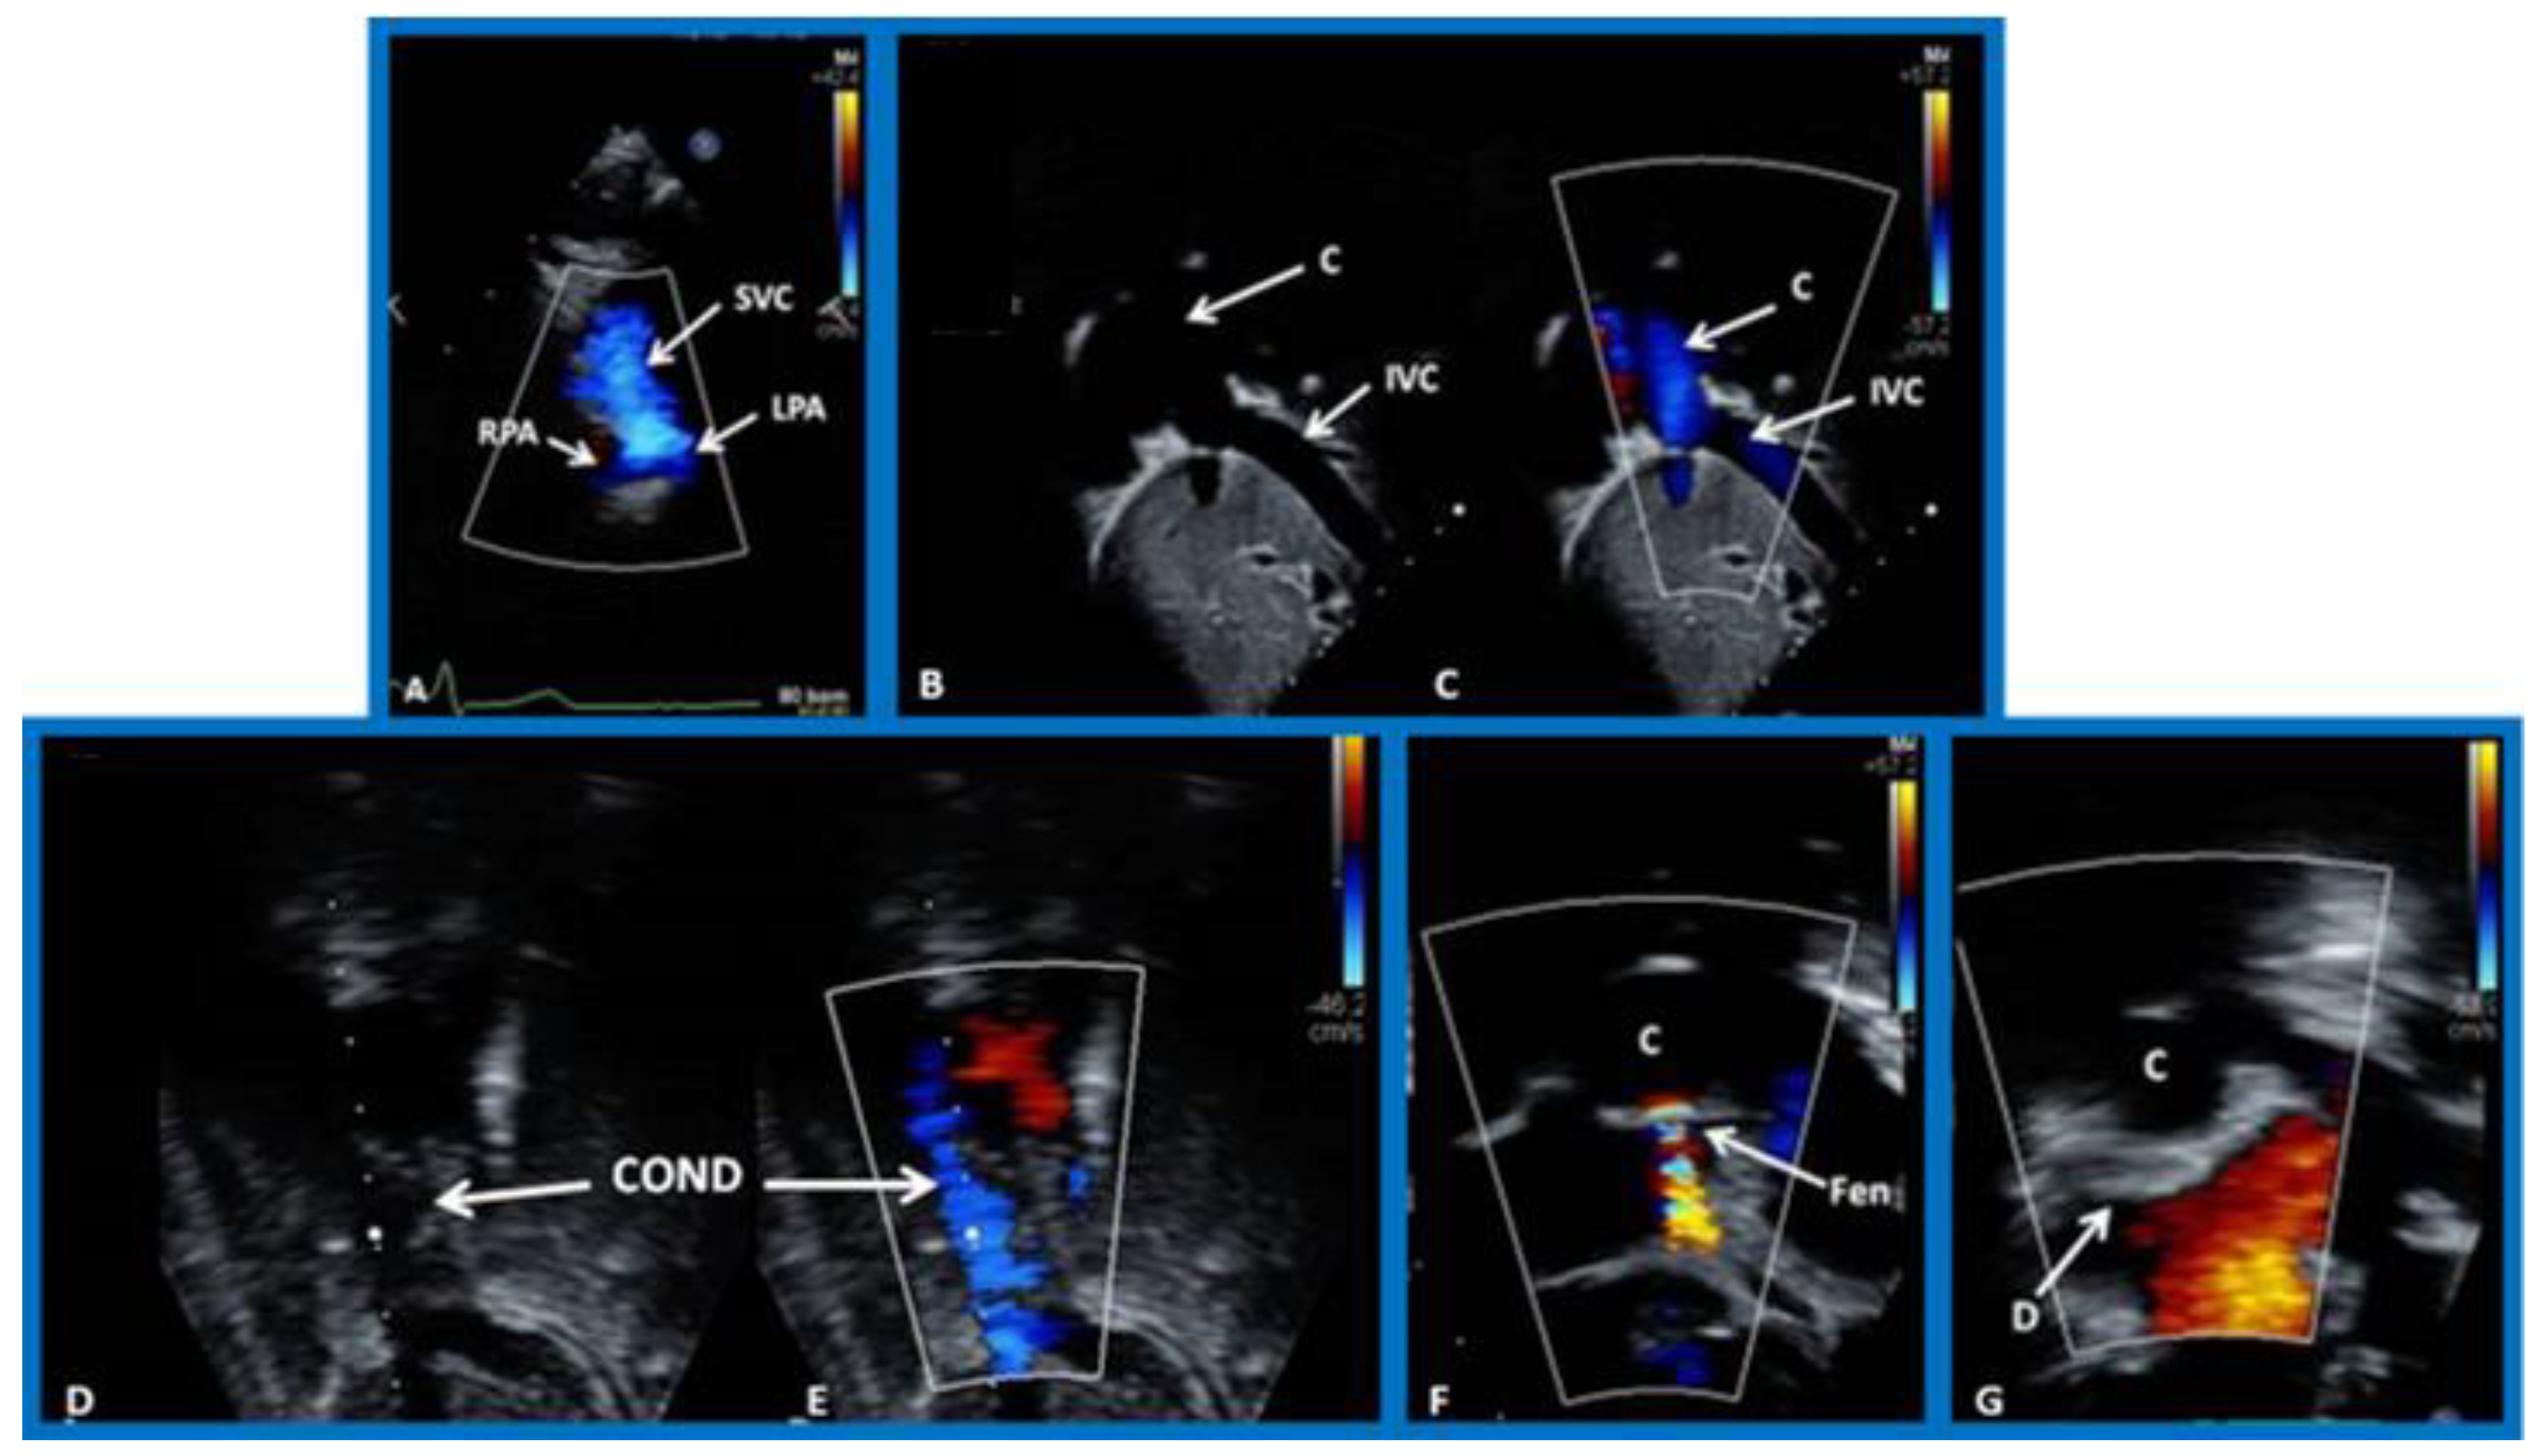

8. Echocardiogram